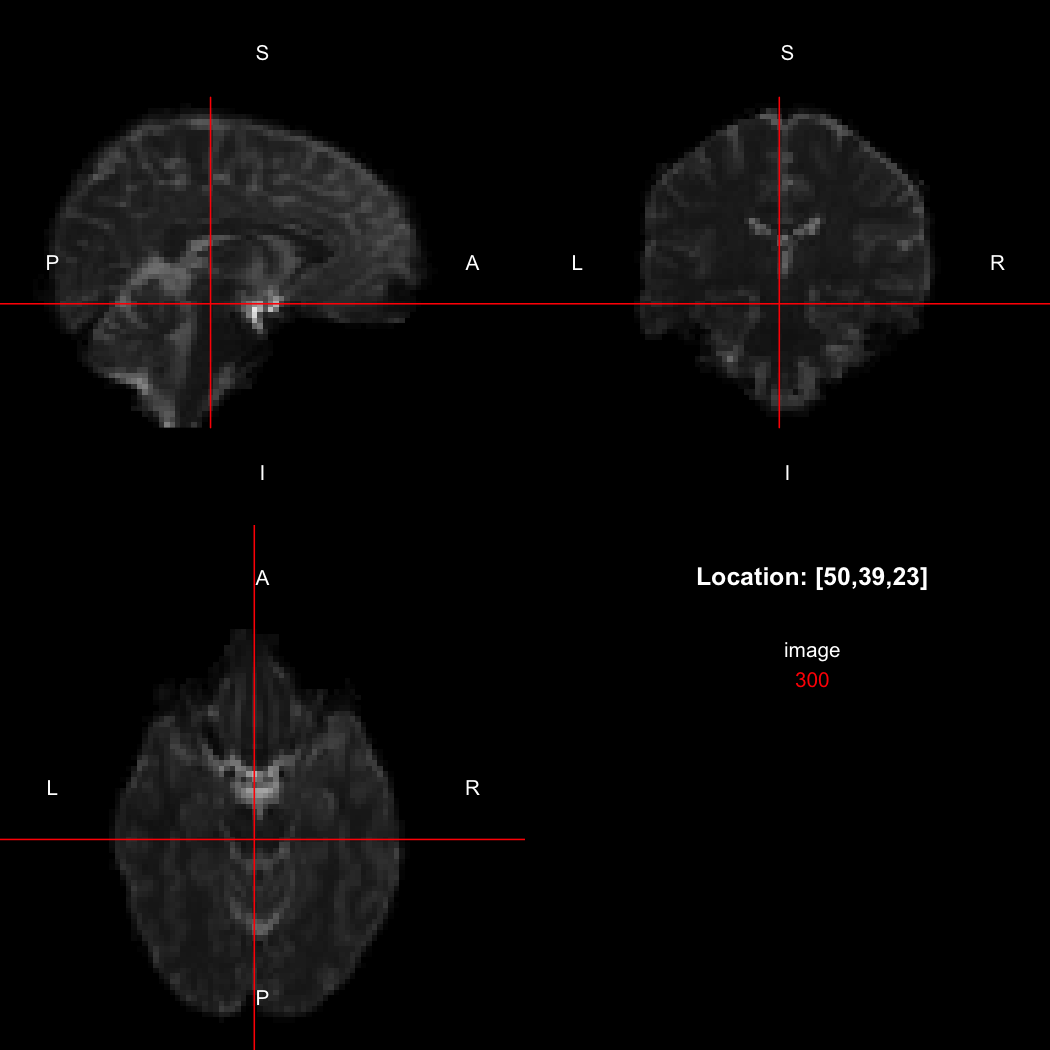

So, here, “LAS” means that the positive x-axis points left, the positive y-axis anterior and the positive z-axis superior. This is the so-called “radiological” orientation convention, and can be requested when viewing images for those who are used to it:

view(image, radiological=TRUE)

plot of chunk unnamed-chunk-12

Notice the left (L) and right (R) labels, relative to the view shown above. Setting the radiologicalView option to TRUE will make this the default for all future views.